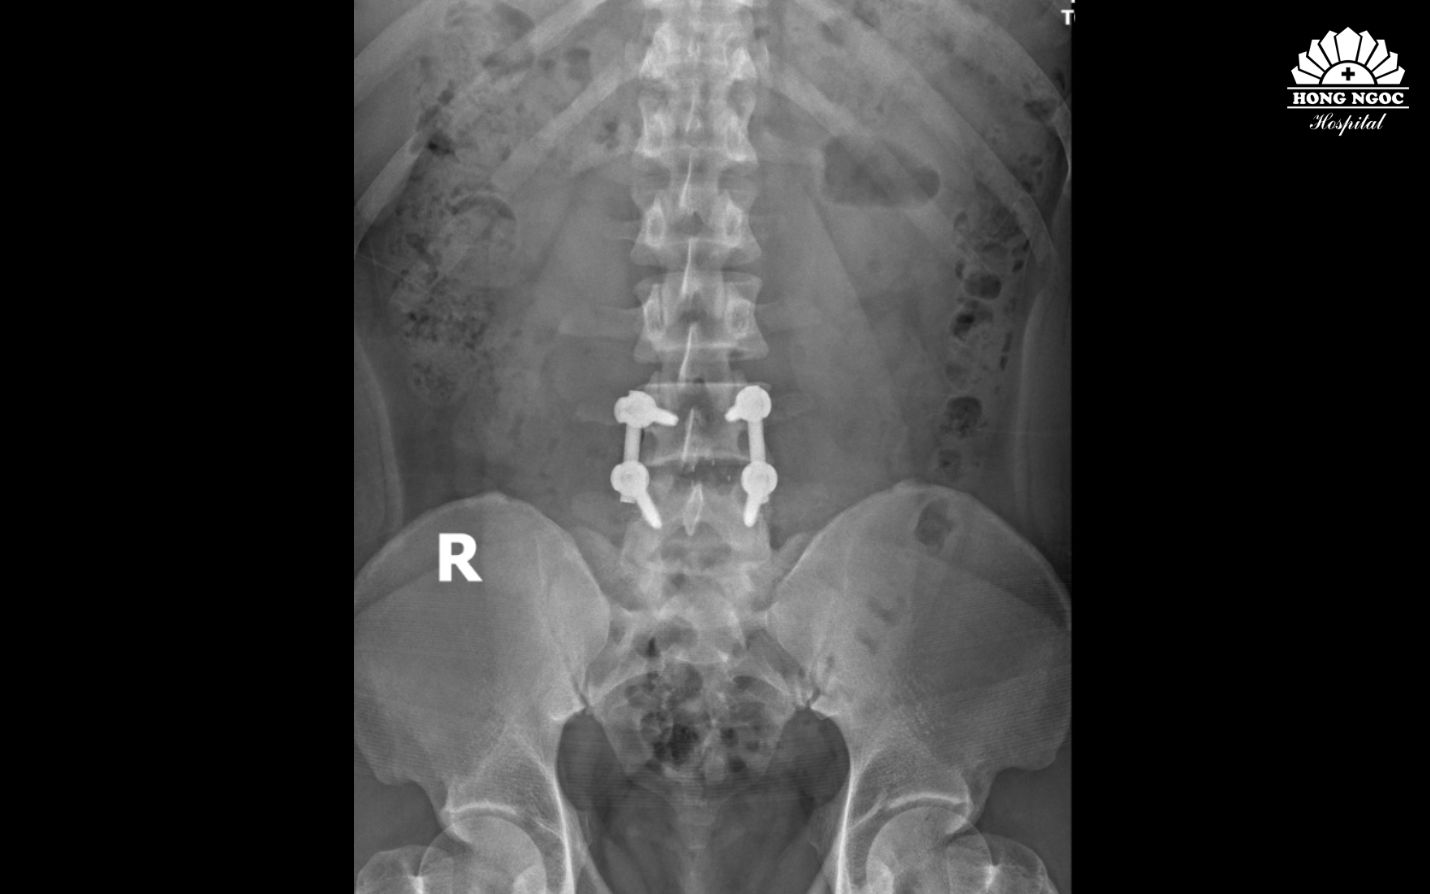

Theo PGS. Hà Kim Trung: Phẫu thuật thoát vị đĩa đệm cột sống thắt lưng thường được chỉ định cho những trường hợp đã điều trị nội khoa không đem lại hiệu quả, khối thoát vị gây rách bao xơ, chèn ép rễ thần kinh, gây rối loạn cảm giác và vận động,... Với người trẻ đang trong độ tuổi lao động, giải pháp tối ưu là phẫu thuật giải phóng chèn ép, kết hợp hàn xương và nẹp vít cố định cột sống, giúp chấm dứt tình trạng đau lưng, phục hồi khả năng vận động, hạn chế nguy cơ tái phát lâu dài. Đặc biệt, phẫu thuật tại vị trí L4/L5 không gây liệt do đốt sống không có tủy.

Phim chụp sau phẫu thuật thoát vị đĩa đệm, hàn xương và nẹp vít đốt sống L4/L5

Dưới sự hỗ trợ của hệ thống C-arm 3D tích hợp trí tuệ nhân tạo, chỉ sau hơn 60 phút, PGS.TS.BS Hà Kim Trung cùng ê - kíp đã phối hợp nhịp nhàng, loại bỏ toàn bộ khối thoát vị mà không gây ảnh hưởng đến các rễ thần kinh xung quanh.